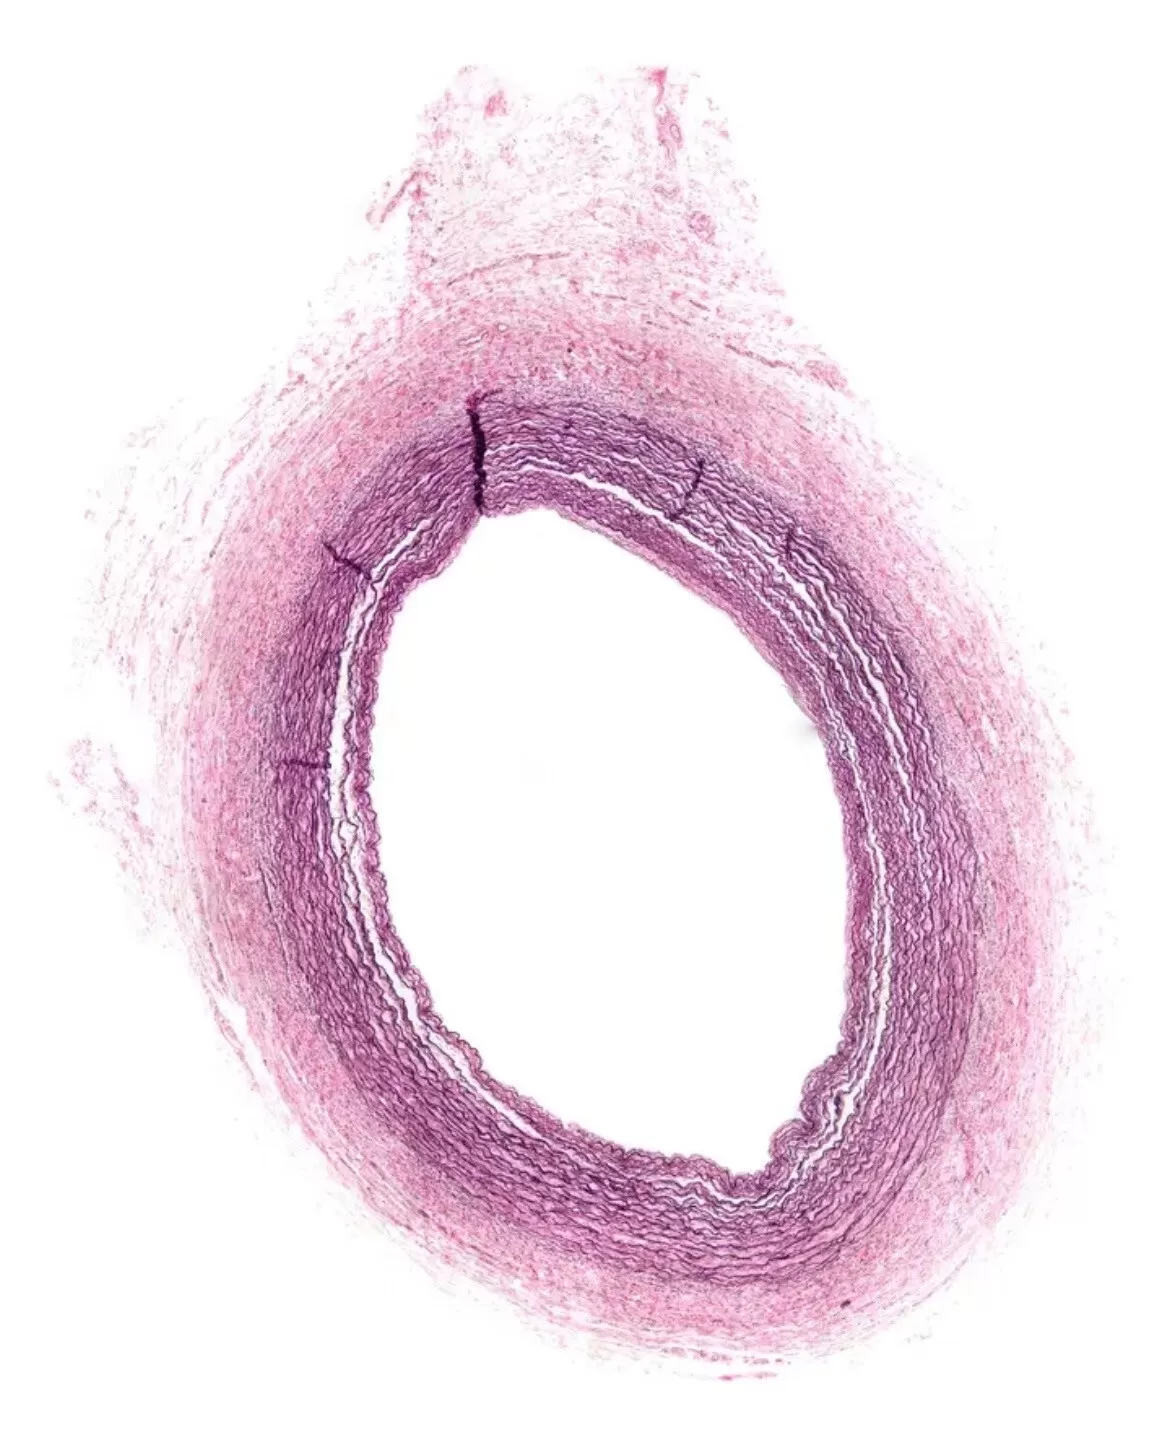

Гистологическое строение артерий разных видов

В стенке артерий выделяют внутреннюю, среднюю и наружную оболочки.

По соотношению гладкомышечных клеток и эластических волокон в средней оболочке артерии делятся:

- Артерии эластического типа (крупные сосуды, выходящие из сердца: аорта и лёгочный ствол) – эластический компонент в средней оболочке сосуда преобладает над гладкомышечными клетками

- Артерии смешанного типа (крупные сосуды, отходящие от аорты: сонные артерии, подключичные артерии, подвздошные артерии) – соотношение эластических волокон и гладкомышечных клеток в стенке сосуда примерно одинаковое

- Артерии мышечного типа (артерии среднего и мелкого калибра, например, к ним относят артерии кожи, скелетных мышц, внутренних органов) – гладкомышечные клетки в средней оболочке сосуда преобладают над эластическим компонентом

Средняя оболочка (tunica media):

- Гладкомышечные клетки

- Эластические волокна: есть свободные эластические волокна/есть окончатые мембраны в виде цилиндров из эластических волокон, которые позволяют быстро менять диаметр просвета сосуда (растягиваются при прохождении объёма крови и «сходятся», когда объём крови в сосуде уменьшается)

Препараты сонной артерии, грудной части аорты и подколенной артерии, окрашенные орсеином. Эластические элементы при этой окраске становятся вишнёвыми. Обратите внимание на разное содержание эластических элементов в артериях разных типов.